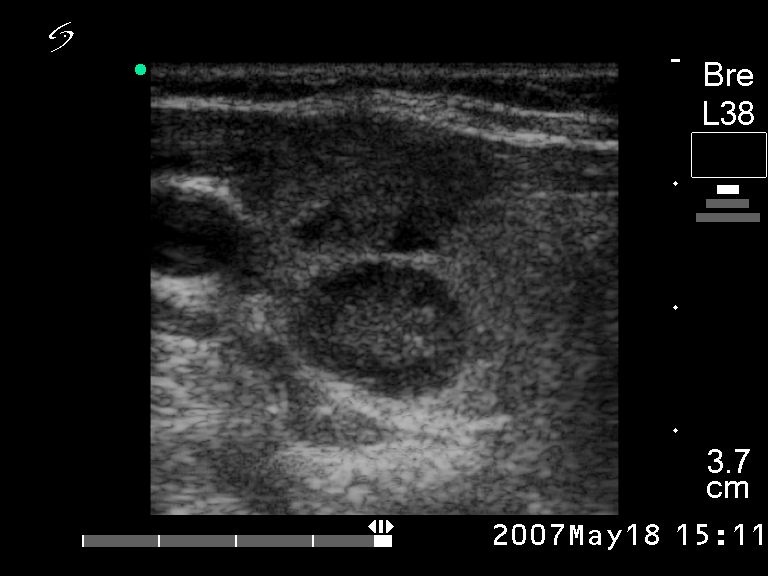

Ultrasonography. There was a hypoechogenic nodule in the right lobe while multiple hypoechogenic lesions were detected in the right side of the neck.